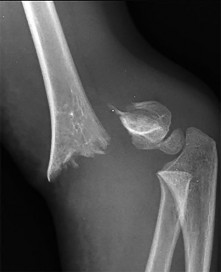

A 5-year-old boy presents with an extension-type Gartland III supracondylar humerus fracture after a fall.

On examination, his hand is well-perfused (pink) with brisk capillary refill, but the radial pulse is absent. What is the most appropriate initial management?